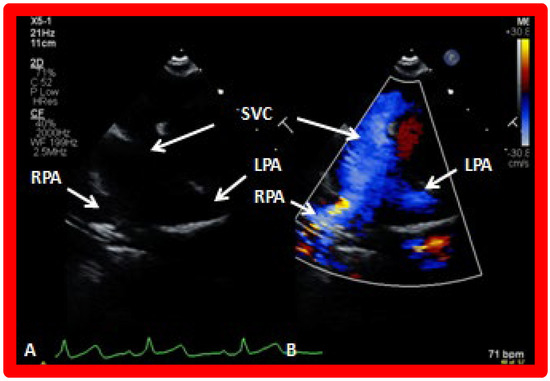

Following bidirectional Glenn, the LV size is likely to decrease (normalize) and LV should maintain normal systolic function. This is because of decreased LV volume overload following bidirectional Glenn and the removal of aorto–pulmonary shunt. The 2D imaging of the bidirectional Glenn is difficult to accomplish, but color flow imaging (Figure 25A, Figure 26B, and Figure 27B) from a suprasternal notch or high parasternal views will help image the bidirectional Glenn. Low pulsed Doppler velocity across the superior vena cava (SVC)–PA junction (Figure 25B and Figure 26C) would indicate no obstruction. Turbulent and high velocity Doppler flow suggests the obstruction of the bidirectional Glenn shunt. The size of the branch PAs may be assessed with a combination of 2D and color flow imaging (Figure 26, Figure 27 and Figure 28).

Figure 26. (A,B) Selected video frames from suprasternal notch view demonstrating bidirectional Glenn shunt. In (A), the right (RPA) and left (LPA) pulmonary arteries are shown by 2D. The superior vena cava (SVC) was not clearly seen. In (B), the SVC is shown emptying into the RPA by color Doppler (B). The LPA did not show color flow because it was in a different plane of imaging than RPA, but is seen by 2D (B). (C) Low Doppler flow velocity across the Glenn shunt indicates unobstructed flow.

Applsci 11 09472 g026

Figure 27. Selected video frames from suprasternal notch view demonstrating bidirectional Glenn shunt; the superior vena cava (SVC) is shown emptying into the right (RPA) and left (LPA) pulmonary arteries by two dimensional (A) and color flow imaging (B). Both RPA and LPA are seen with color in contrast to that seen in Figure 26, probably related to both pulmonary arteries are in a similar echo plane.